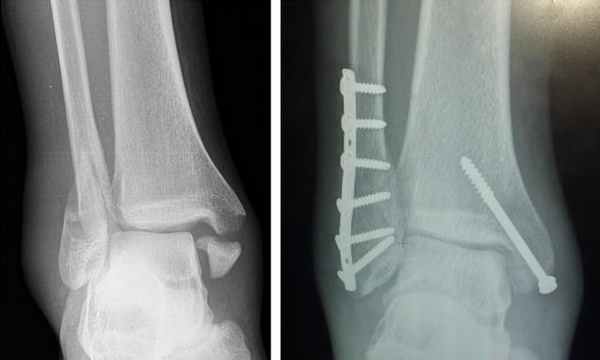

В случае, когда после выполнения закрытого вправления перелома лодыжки смещение сохраняется, то необходимо неотложное оперативное восстановление точных взаимоотношений между элементами в суставе. Операция — остеосинтез костных отломков применяется для восстановления анатомии голеностопного сустава. На сегодняшний день в нашем центре применяются передовые технологии, материалы, новые хирургические методики в оперативном лечении переломов лодыжек. Это необходимо для того, чтобы достичь хорошего функционального результата и предотвратить инвалидизацию человека и формирование деформирующего артроза голеностопного сустава в будущем.

Фото — извлечение металлоконструкции после перелома лодыжки

рентгенограмма ноги с

установленной металлоконструкцией